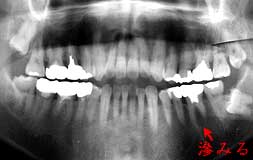

初診時 パノラマ |4567部 拡大

歯槽骨吸収は中程度で年齢の割には良好

|7は歯髄に達するカリエス存在

初診時口腔内およびX線所見:

口腔清掃状態はやや不良。全体に中程度以上の歯槽骨吸収が認められたが、年齢の割には良好。 主訴の「56は、無髄歯で打診痛もなし。レントゲン診査により、|7に深いカリエスが認められた が、打診痛や知覚過敏様の症状は認められなかった。

処置および経過:

「どこが痛いか分からない」という訴えであれば、当初より|7の歯髄炎を疑って治療 したはずであるが、どうしても「56と言い切るので、歯肉炎症による知覚過敏を疑って、全体の スケーリングと、「56の徹底したスケーリングを行って初診時の治療を終了。  2日後、「下の知覚過敏は治まりましたが、今度は上の歯が痛くなってきました。」と来院。 当初より疑いのあった|7の抜髄を行い症状は改善。

考察:

無髄歯の知覚過敏は日常臨床で、それ程珍しいケースではない。歯石沈着に伴う歯肉の炎症や 根尖病巣が原因で『滲みる』と感じるものと思われる。  本症例において、以前から滲みていたのは無髄歯の「56であったと推測される。その滲みから 継続して痛みを感じるようになったために「56が痛いと感じるようになったのか、実際に「56が痛か ったのかは不明である。|7も初診時から痛みがあったのか、スケーリング等の刺激により たまたま翌日から痛みを発するようになったのかも不明のままである。

何れにしても、無髄歯が滲みるという事実と、上顎大臼歯部の歯髄炎は下顎の痛みと混同し 易い事実を十分把握しておく必要がある。

|7は、レントゲンでカリエスの存在を確信できる状態であったにも関わらず、肉眼での 所見では全くカリエスの存在が分からない歯でした。